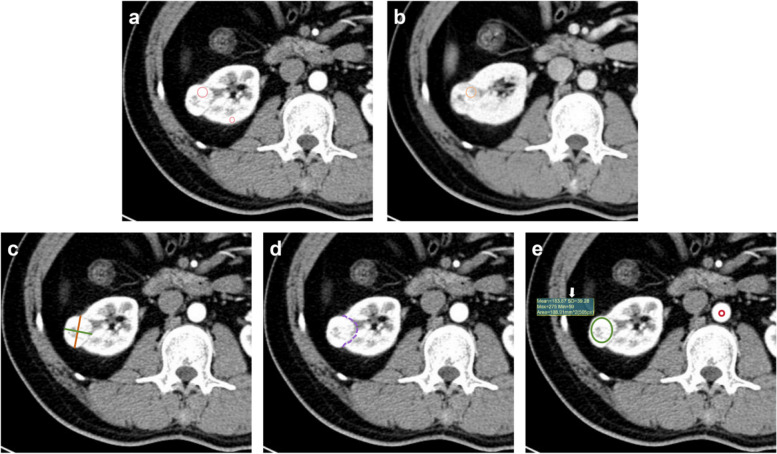

Methods: A retrospective collection of 331 patients with pathologically confirmed renal masses were enrolled in this study. Two radiologists independently assessed the CT images: in addition to heterogeneity score (HS) and mass-to-cortex corticomedullary attenuation ratio (MCAR), measured parameters included ratio of major diameter to minor diameter at the maximum axial section (Major axis / Minor axis), tumor-renal interface, standardized heterogeneity ratio (SHR), and standardized nephrographic reduction rate (SNRR). Spearman's correlation analysis was performed to evaluate the relationship between SHR and HS. Univariate and multivariate logistic regression analyses were employed to identify independent risk factors and then CT-score was adjusted by those indicators. The diagnostic efficacy of the modified CT-scores was evaluated using ROC curve analysis.

Results: The SHR and heterogeneity grade (HG) of mass were correlated positively with the HS (R = 0.749, 0.730, all P < 0.001). Logistic regression analysis determined that the Major axis / Minor axis (> 1.16), the tumor-renal interface (> 22.3 mm), and the SNRR (> 0.16) as additional independent risk factors to combine with HS and MCAR. Compared to the original CT-score, the two CT algorithms combined tumor-renal interface and SNRR showed significantly improved diagnostic efficacy for ccRCC (AUC: 0.770 vs. 0.861 and 0.862, all P < 0.001). The inter-observer agreement for HG was higher than that for HS (weighted Kappa coefficient: 0.797 vs. 0.722). The consistency of modified CT-score was also superior to original CT-score (weighted Kappa coefficient: 0.935 vs. 0.878).